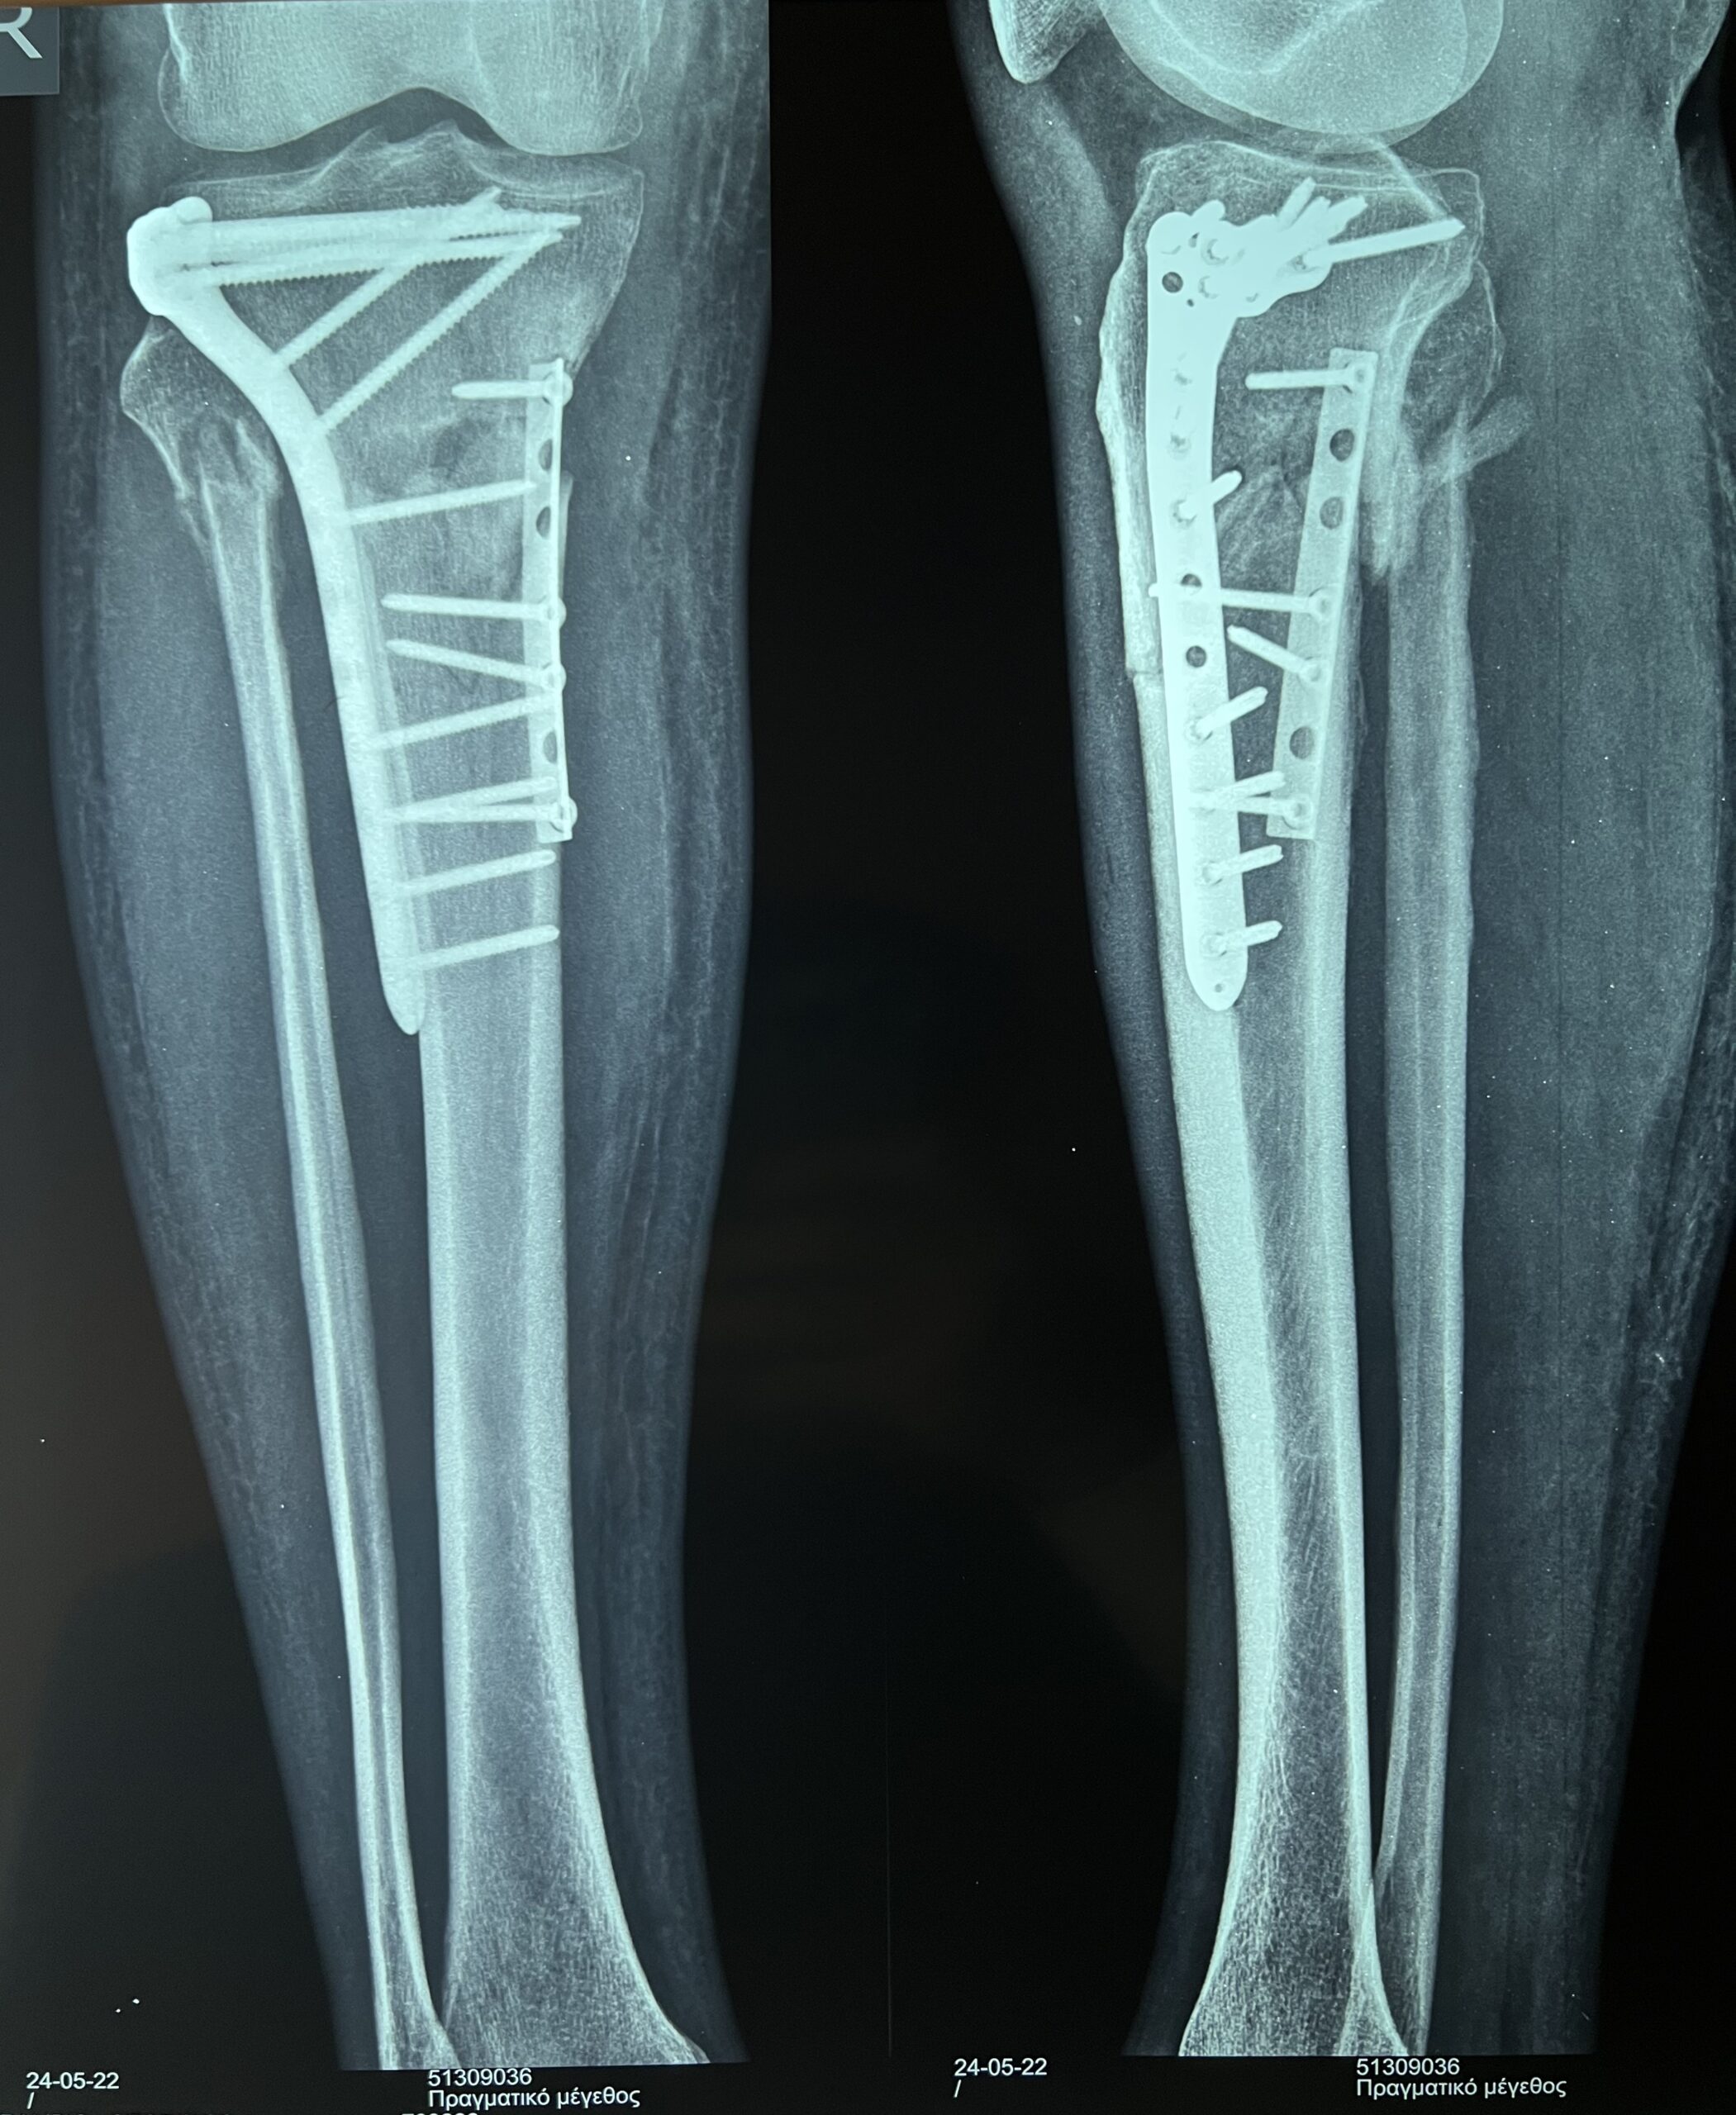

Η διάγνωση ενός κατάγματος κνημιαίου plateau πραγματοποιείται από έναν έμπειρο Ορθοπαιδικό. Αρχικά η λήψη ενός λεπτομερούς ιστορικού και η κλινική εξέταση του ασθενούς είναι απαραίτητα. Στην συνέχεια για την διάγνωση αλλά και την ταξινόμηση του κατάγματος είναι υποχρεωτική η διενέργεια ακτινολογικού ελέγχου. Ο έλεγχος αυτός περιλαμβάνει απλές ακτινογραφίες (φας, προφιλ και λοξές) ενώ πολλές φορές απαιτείται περαιτέρω διερεύνηση με αξονική τομογραφία για την πλήρη κατανόηση της μορφής του κατάγματος και τον σωστό προεγχειρητικό σχεδιασμό.

Σε κατάγματα του κνημιαίου plateau με μεγάλη συντριβή, με εμβύθιση της αρθρικής επιφανειας ή σε ασθενείς με αθλητική δραστηριότητα συστήνεται η χειρουργική αντιμετώπιση. Αυτή συνίσταται στην ανοικτή ανάταξη του κατάγματος και την εσωτερική οστεοσύνθεση του (τοποθέτηση πλάκας και βιδών), την τοποθέτηση εξωτερικής οστεοσύνθεσης ή στον συνδυασμό μεθόδων. Σε επιλεγμένα περιστατικά μπορεί να γίνει η ανάταξη του κατάγματος υπό αθροσκοπικό έλεγχο.